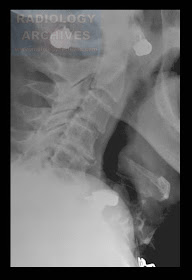

Ξένο Σώμα (Τεχνητή Οδοντοστοιχία) στον Απιοειδή Βόθρο

Foreign Body in the Pyriform Sinus (Denture)